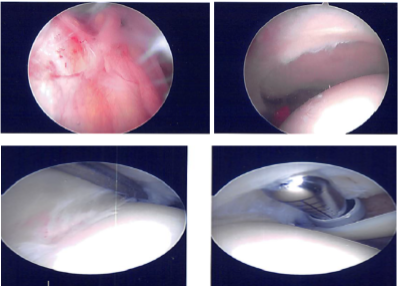

Lateral entry portal was made. The scope was entered. Examination of the glenohumeral joint showed extensive synovitis, degenerative arthritis of the glenohumeral joint more on the humeral head, absence of biceps and the rotator cuff tear in the region of supraspinatus and in infraspinatus.

An anterior entry portal was made and shaver was introduced and debridement of the synovitis was performed. Chondroplasty of the humeral head as well as the glenoid was also performed. The scope was entered from the anterior portal and findings were re-confirmed and debridement was completed.

The scope was entered in the subacromial space. A limited examination tear was found in the supra and Infraspinatus region. Debridement was done and bursa was removed. There was acromial spur anteriorly. The spur was removed by the use of a burr.

Acromioplasty was performed. A decision was made to repair the rotator cuff. An accessory left portal was made. The footprint for the rotator cuff was debrided using a burr exposing the subcortical bone. Then, a 4.5 mm with four tails was used and Inserted Into the humeral head following and tapped.

All the four tails were passed through the rotator cuff sequentially from anterior to posterior edge. The tails were tied over each onto itself using a sliding knot. The rotator cuff was well opposed. Final pictures were taken and the shoulder was irrigated.

Intraoperative Arthroscopy Images